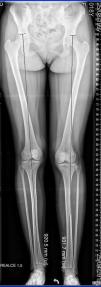

La medición radiológica fue realizada sobre telemetrías de miembros inferiores. La medición de la asimetría inicial (última radiografía previa a la cirugía) y residual (postepifisiodesis en el momento de la madurez esquelética) fue realizada por un único observador entrenado con un error técnico de medición (ETM) de 1,1 mm. En la figura 1 se muestran las reparos radiológicos para la medición de miembros inferiores, siguiendo los criterios descritos por Sánchez16.

Otro observador entrenado (JC) registró las complicaciones posquirúrgicas. Estas se dividieron en perioperatorias inmediatas y alejadas. Se definió sobre corrección cuando se invirtió la asimetría en la adultez en más de 1 cm18. Para la evaluación de la deformidad angular del miembro operado se utilizaron las zonas o cuadrantes del eje mecánico, como muestra la figura 2.19 Se consideró alteración del eje mecánico como complicación posquirúrgica si la desviación de este no estaba presente en la radiografía inicial o esta había aumentado más de 1 cuadrante o había cambiado de zona.